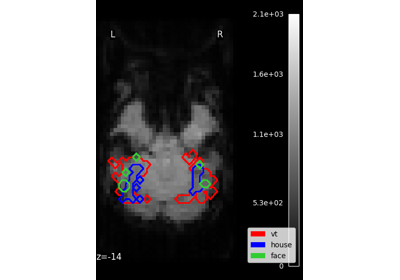

Plot Haxby masks